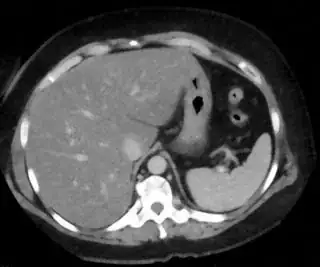

Below are some of the opened and segmented images. Of course there's more to be done in terms of

- separating out the liver region

- generalizing this to a large dataset

but hope this is at least a starting point.

You might be able to narrow down the region or interest by filtering out the darkest and the lightest regions from the segmented image. For this, use the k-means cluster centers, check for the extreme values (max and min) and remove the corresponding k values from the labeled image. Then you can look for large structures to the left of the result image. Worst case, you might get a hole on the left side when the extreme region filtering goes wrong. I've updated the code and results.